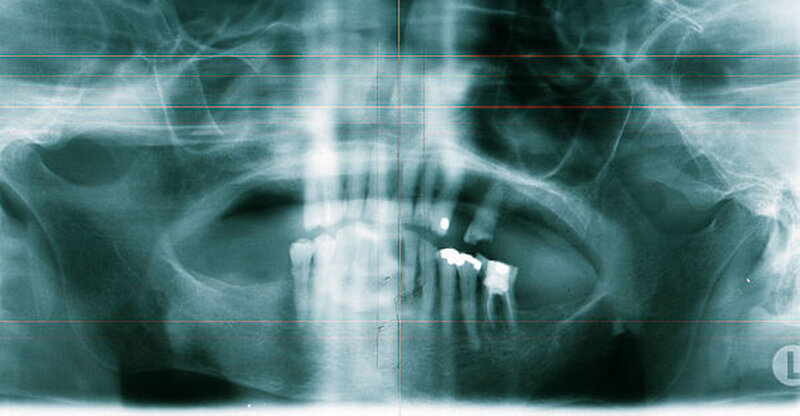

In der digitalen Volumentomografie fiel ein osteolytischer Prozess in der Oberkiefermolarenregion links auf, wobei die bukkale Kompakta weitstreckig unterbrochen war bei noch intakter lateraler und basaler Kieferhöhlenbegrenzung. In einzelnen Schichten tunnelierten die osteolytischen Bereiche die Kompakta (Abbildung 3).

Radiologisch stellen sich braune Tumore als Osteolysen dar, wobei der Knochen bei entsprechender Größe des Befunds auftreiben kann. Häufig zu erkennen ist eine Auflockerung und Rarefizierung der Spongiosa. Die Kompakta kann ausgedünnt sein beziehungsweise völlig fehlen, wobei es häufig zu Tunnelierungen kommt. Das bedeutet, dass die Spongiosa radiologisch stärker affektiert erscheint als die darüber befindliche Kompakta [Freyschmidt, Ostertag et al., 2010].